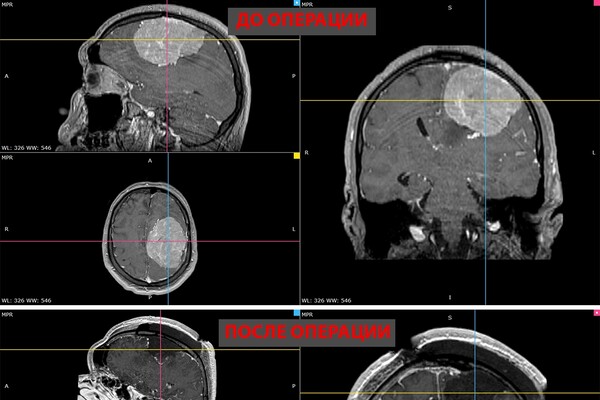

В Новосибирске врачи удалили 35-летнему пациенту гигантскую опухоль головного мозга. Об этом сообщает пресс-служба НМИЦ имени Мешалкина Минздрава России.

В ноябре прошлого года у мужчины появилась слабость в правой руке и затруднения речи — МРТ выявила у него менингиому диаметром более восьми сантиметров в левом полушарии мозга. К концу года рука практически перестала работать, ходьба давалась пациенту с трудом.

Уже в январе, когда мужчина готовился к плановой операции, у него выявили тромбоэмболию легочной артерии. Из-за высокого риска осложнений в нейрохирургическом лечении ему отказали.

Тем временем его симптомы нарастали — появились эпилептические приступы с потерей сознания и судорогами. Семья обращалась в разные клиники, но согласилась принять пациента только НМИЦ Мешалкина, где одновременно занимаются нейрохирургией и лечением тромбоэмболии.

«Когда его привезли, он уже был наполовину парализован, приступы стали ежедневными. Ждать было нельзя», — рассказал нейрохирург.

Консилиум с кардиологами и кардиохирургами решил, что пациенту можно провести операцию. Его доставили в Новосибирск в сопровождении врачей, а на второй день после поступления прооперировали.

Пятичасовая операция прошла успешно. Опухоль удалили полностью. Уже на следующий день появились движения в руке, через две недели пациент снова стал сам ходить. У него восстановились речь и движения, приступы исчезли.